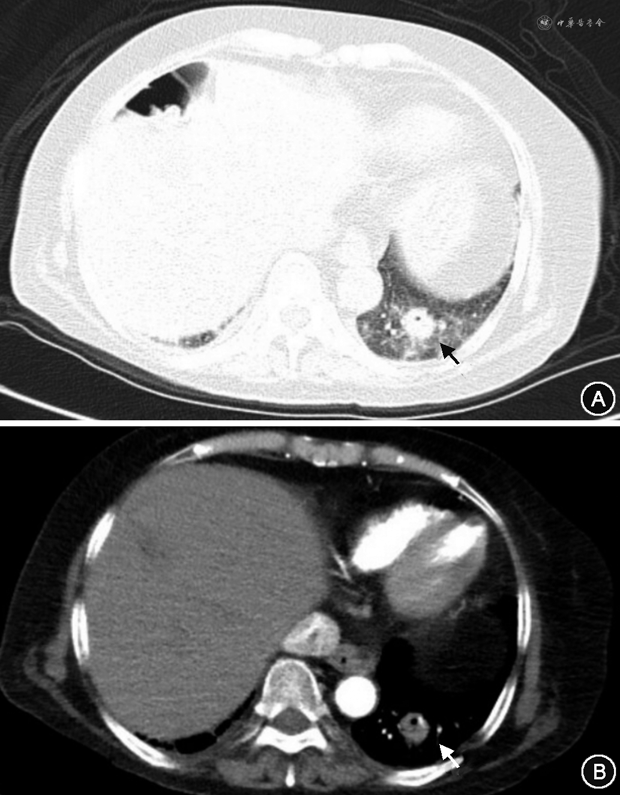

入院次日患者诉头晕、呼吸困难,测 SpO2 92%(未吸氧),血气示pH 7.45,氧分压 67 mmHg,二氧化碳分压32 mmHg,乳酸 4.4 mmol/L,心肌肌钙蛋白(cTnI)正常范围,N末端B型钠尿肽原(NT-proBNP)281 pg/ml,超声示双侧股浅静脉至胫后静脉起始段血栓形成。CT肺动脉造影(CTPA)示右肺动脉主干及双肺多发分支栓塞(图2),左肺下叶团片影伴小空泡(图3);胆囊底壁局限性缩窄(图4A)。监测患者血压显著降至85/63 mmHg,持续时间>15 min,心率90 次/min,呼吸25 次/min,意识清晰,考虑为急性肺栓塞,肺栓塞严重程度指数(PESI)评分至少为100分,简化的肺栓塞严重程度指数(sPESI)评分至少1分,血流动力学不稳定,危险分层为高危。转入监护病房后血压逐渐回升至125/66 mmHg,予普通肝素持续静脉泵入,维持APTT 50 s左右,呼吸困难缓解,3日后改为依诺肝素钠4 000 U每12小时皮下注射。

2020年11月11日转入呼吸内科继续治疗,皮肌炎方面维持甲泼尼龙20 mg/d口服。完善肌炎抗体谱示:抗伴抗小泛素样修饰物活化酶(SAE)抗体、抗Ro-52抗体阳性。腹部超声示脂肪肝,胆囊体部囊壁增厚;双大腿MRI示肌肉萎缩;肌电图示肌源性损害。考虑皮肌炎为肿瘤相关性皮肌炎可能性大,原发灶未明。多学科讨论认为患者肺部病变有恶性可能,但血供丰富不宜穿刺活检;而胆囊形态异常结合CA19-9明显升高,恶性病变可能性更大。进一步行腹部增强CT(图4B),见胆囊形态欠规则,壁不均匀增厚伴异常强化,考虑恶性可能;肝可疑低强化结节,转移待除外;胰头后方多发肿大淋巴结。PET-CT示胆囊底壁不规则增厚恶性可能性大,胰头后方淋巴结转移可能性大,肝脏未提示;左肺下叶片影炎性病变可能性大。综上,患者胆囊来源的恶性病变可以解释病情全貌。基本外科认为目前肿瘤所致症状及合并症突出,虽不能除外局部转移,但行胆囊切除手术方有根治机会。